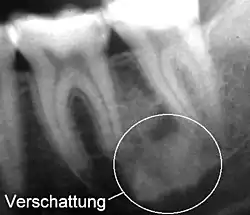

Eine Verschattung (auch Radioopazität) ist ein heller und eine Aufhellung (Radioluzenz) ein dunkler Bereich auf einem Röntgenbild.[1] Grund ist die unterschiedliche Röntgenopazität von Gewebearten.

Da die Begriffe aus der Ära des Fluoreszenzradiographie beibehalten wurden, liegt ein scheinbares Paradoxon vor. Es wird also ein Bereich auf dem Röntgenfilm, der heller ist, als er sein sollte, verschattet genannt und ein Bereich, der dunkler ist, als er sein sollte, aufgehellt genannt.